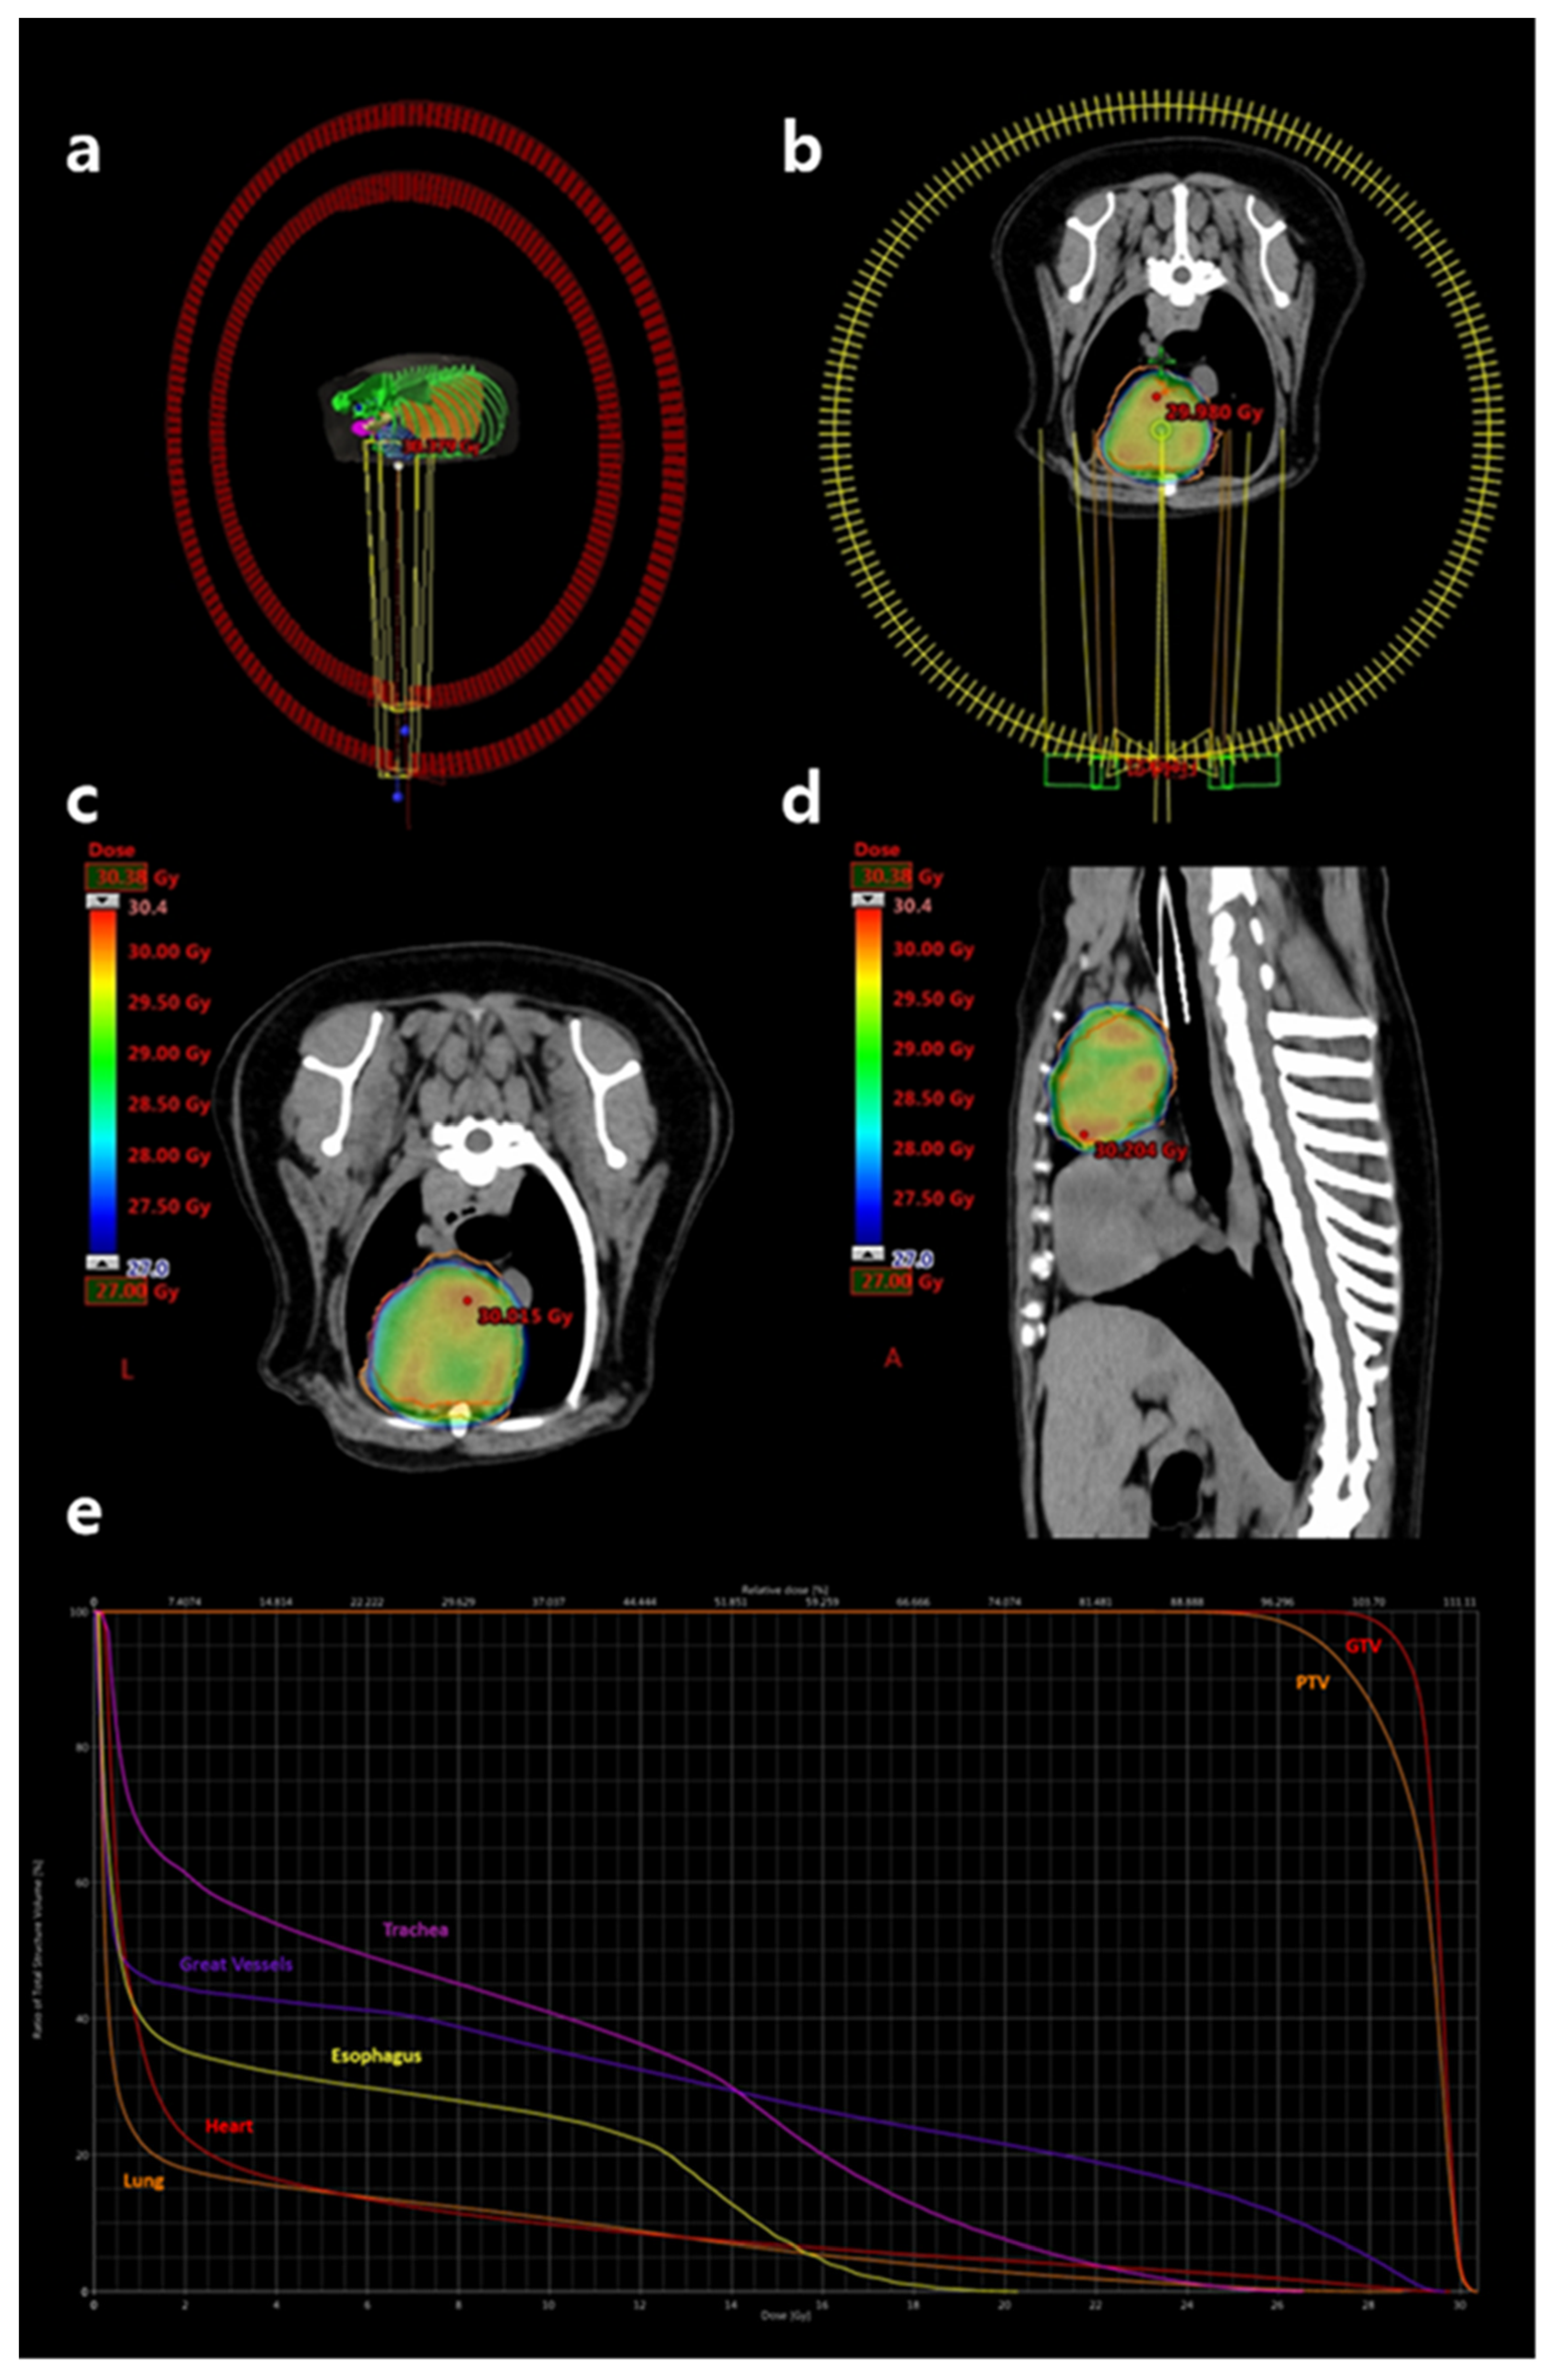

SBRT was planned using VMAT and delivered via a 6 MV linear accelerator equipped with 5-mm multileaf collimators (Clinac iX; Varian Medical Systems, Palo Alto, CA, USA). Inverse treatment planning was performed using Eclipse™ software version 13.7.33 (Varian Medical Systems). A total dose of 27 Gy was prescribed in three fractions of 9 Gy, administered on alternate days. Two full-arc coplanar VMAT beams were used to optimize target coverage and dose conformity (Figure 3a,b).

The gross tumor volume (GTV) was defined as the contrast-enhancing portion of the cranial mediastinal mass. The planning target volume (PTV) was generated by applying a 3-mm isotropic expansion to the GTV to account for setup uncertainties and organ motion. Portions of the PTV overlapping sensitive organs at risk (OARs), including the heart, lungs, major vessels, and trachea, were cropped to limit dose delivery to these structures. The clinical target volume (CTV) was not defined. Dose planning ensured that 100% of the prescribed dose encompassed at least 95% of the PTV and 99% of the GTV. Organs at risk—including lungs, heart, esophagus, trachea, major vessels, bronchi, and spinal cord—were contoured and evaluated to meet appropriate dose constraints (Figure 3c–e). Dose constraints were established with reference to published human SBRT guidelines for three-fraction regimens [13,14,15]. Supplementary Table S1 summarizes the OAR dose constraints applied. The volumes of target structures and calculated radiation doses/volumes to those structures are summarized in Table 1.

Figure 3. Radiation therapy planning performed using the Eclipse™ software version 13.7.33. (a,b) Schematic representations of the two coplanar 360-degree volumetric arcs used for stereotactic treatment. One arc rotates in a clockwise direction and the other in a counterclockwise direction. (c) Transverse and (d) sagittal views of the dose distribution over the cranial mediastinal mass. The dose color wash represents regions receiving doses equal to or greater than prescribed dose of 27 Gy, with the red dot indicating the maximum dose hotspot on the corresponding slice. (e) Dose–volume histogram illustrating target coverage and organ-at-risk sparing. From left to right: lung (orange), heart (red), esophagus (yellow), great vessels (purple), trachea (pink), PTV (orange), and GTV (red). The plan ensured that a minimum of 99% of the GTV and 95% of the PTV received at least 27 Gy. GTV, gross tumor volume; PTV, planning target volume.